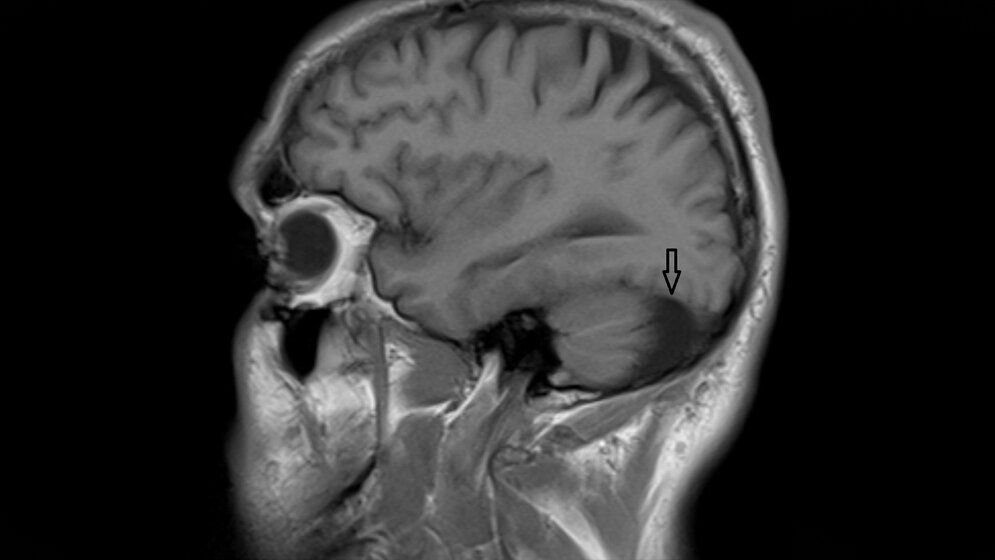

Arachnoidalzysten stellen etwa 1 % der intrakraniellen Raumforderungen dar. Der Mechanismus der Zystenvergrößerung wird kontrovers diskutiert. Der Gehalt an Proteinen der Arachnoidalzysten und des zerebrospinalen Liquors erscheint relativ ähnlich, doch gibt es eine bestimmte Anzahl an Proteinen, die sich signifikant unterscheiden. Das kann auf eine Veränderung der Proteine durch den Füllmechanismus oder auf eine Wirkung der Zystenmembran zurückzuführen sein. Bei Patienten mit Cluster-Kopfschmerz sollte eine KM-assistierte MRT bei normaler neurologischer Untersuchung erfolgen.

Arachnoid cysts are common, accounting for approximately 1 % of intracranial mass lesions. The mechanism of enlargement of arachnoid cysts is controversial. The protein content of arachnoid cyst fluid and cerebrospinal fluid appears to be similar. There are proteins that were significantly differentially abundant between arachnoid cyst fluid and cerebrospinal fluid. This could reflect the possibility that these proteins are affected by the filling mechanism of arachnoid cysts or are shed from the membranes into arachnoid cyst fluid. Neuroimaging, preferably contrast-enhanced magnetic resonance imaging should always be considered in patients with cluster headache despite normal neurological examination.